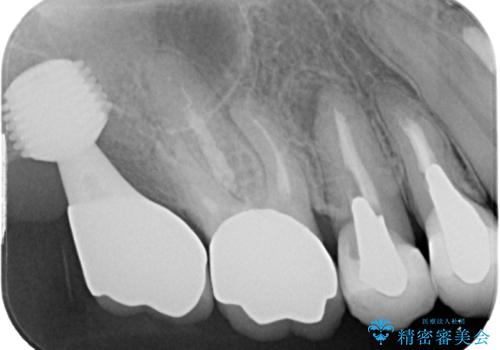

抜歯後2ヶ月でのインプラント埋入を行いましたが、骨の再生は不十分でした。

骨量は不十分でしたが、デンサーバーを用いることで無事に埋入することができ、その後は速やかに補綴治療を行うことができました。